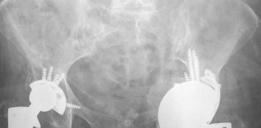

Postoperative Radiographs

(Figs. 20.12 and 20.13)

(7) Place cage into the acetabular cup and secure with screws to the socket as well the ilium. (8) Trial accordingly to restore leg length and soft-tissue tension (Figs. 20.12 and 20.13).

Reconstruction techniques: Bone grafting, implanting jumbo highly porous metal cup, securing cage construct into cup and host bone and restoring hip centre, length and stability with construct (including cup cage and femoral head size/length).